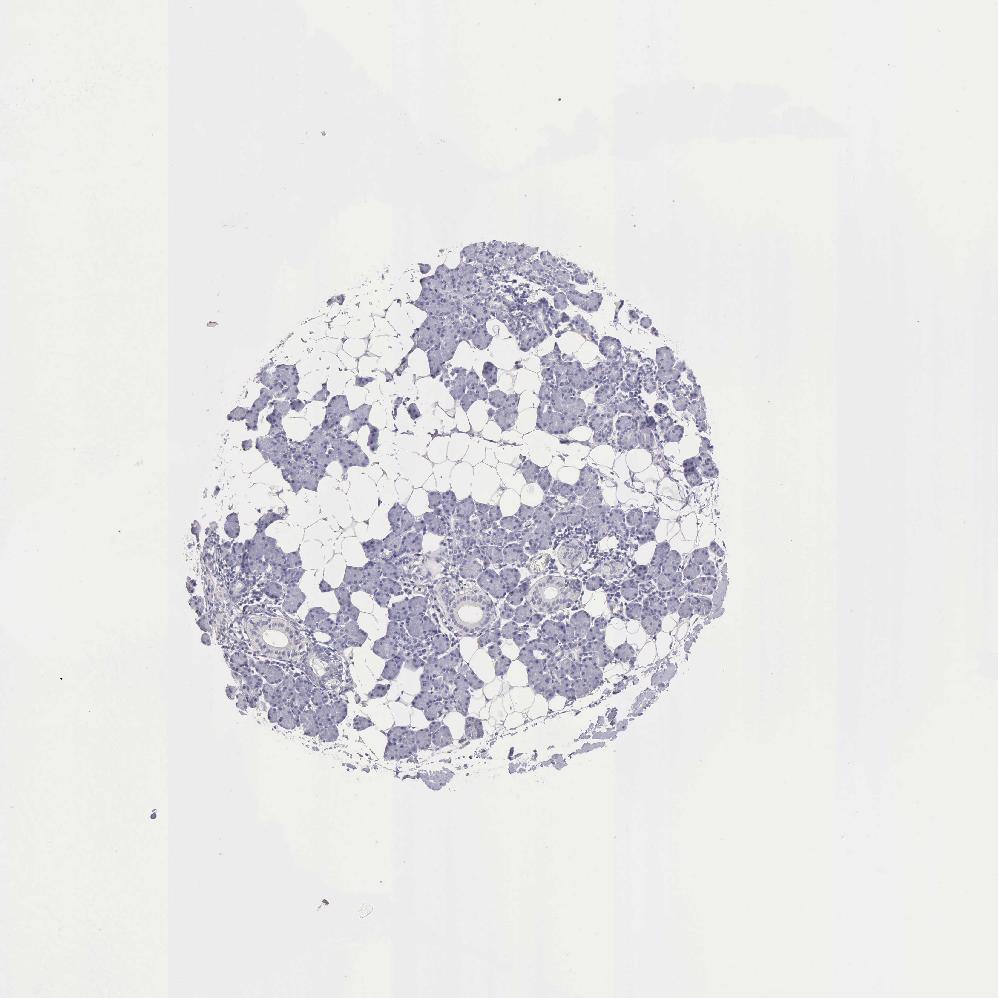

SALIVARY GLAND - Antibody stainingi

Antibody staining in the annotated cell types in the current human tissue is reported as not detected, low, medium, or high, based on conventional immunohistochemistry profiling in selected tissues. This score is based on the combination of the staining intensity and fraction of stained cells.

Each image is clickable and will lead to virtual microscopy that enables deeper exploration of all samples and also displays staining intensity scores, fraction scores and subcellular localization as well as patient and tissue information for each sample.

Antibody HPA001066

Glandular cells Not detected